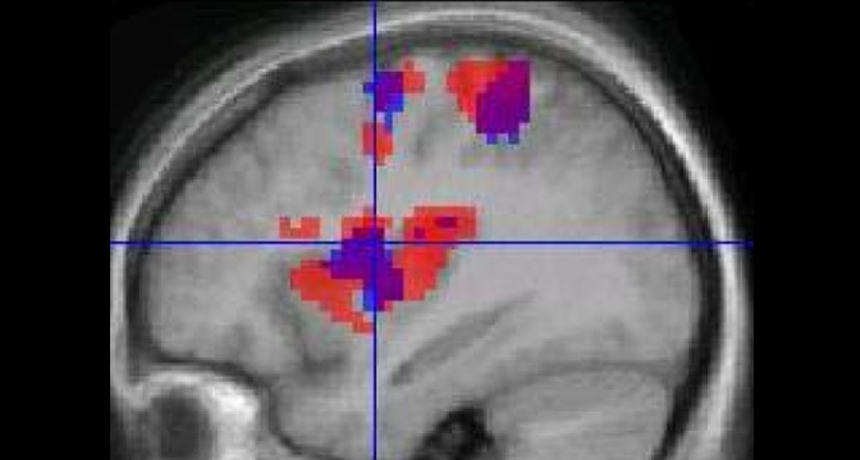

GO WITH THE FLOW  Functional MRI scans use blood flow (colors represent changes in blood flow) to indicate nerve cell behavior, but those two things aren’t always coupled, a new study finds.

K. Roberts et al/BMC Anesthesiol. 2008/Open-I (CC BY 2.0)

A mainstay of many neuroscience labs, functional MRI relies on blood flow changes in the brain to serve as proxies for active nerve cells.